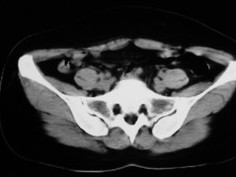

女42岁肛门下坠感4月余.

子宫轻度右倾,体后方见小似新月形低密度区,边界清楚。余所见无明显异常。

考虑:子宫直肠窝少量积液(盆腔炎所致)。

子宫轻度右倾,体后方见小似新月形低密度区,道格拉斯窝周围间隙欠清晰,有索条模糊影阴,多考虑:肛周脓肿可能性大。

子宫轻度右倾,体后方见小似新月形低密度区,道格拉斯窝周围间隙欠清晰,有索条模糊影阴,多考虑:肛周慢性感染可能。